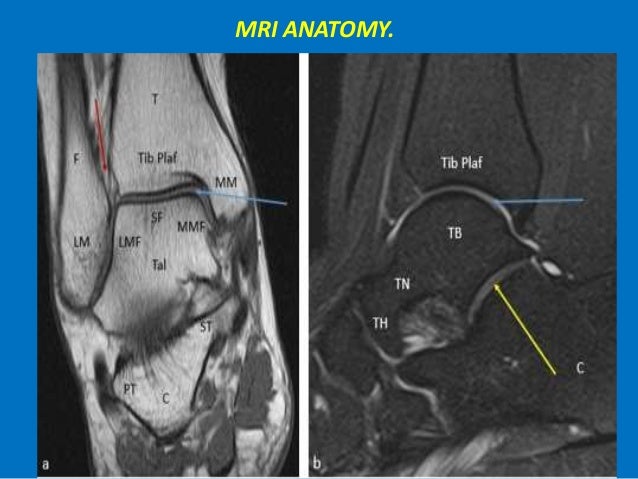

Ankle mri anatomy. It carries the weight of the body and can undergo a myriad of pathology most commonly traumatic injuries of the medial and lateral malleoli. There are several bones that make up the ankle. Mri anatomy of the ankle tendons and ligaments normal mri tendon anatomy tendons around the ankle are divided into four groups.

Mri of the ankle. Mri of the ankle and feet. Three ligamentous groups support the ankle joint.

Start your exam with fatsat images of the bones to screen for edema. The tibia the fibula the talus and the calcaneus. The ankle joint is comprised of the tibia fibula and talus as well as the supporting ligaments muscles and neurovascular bundles.